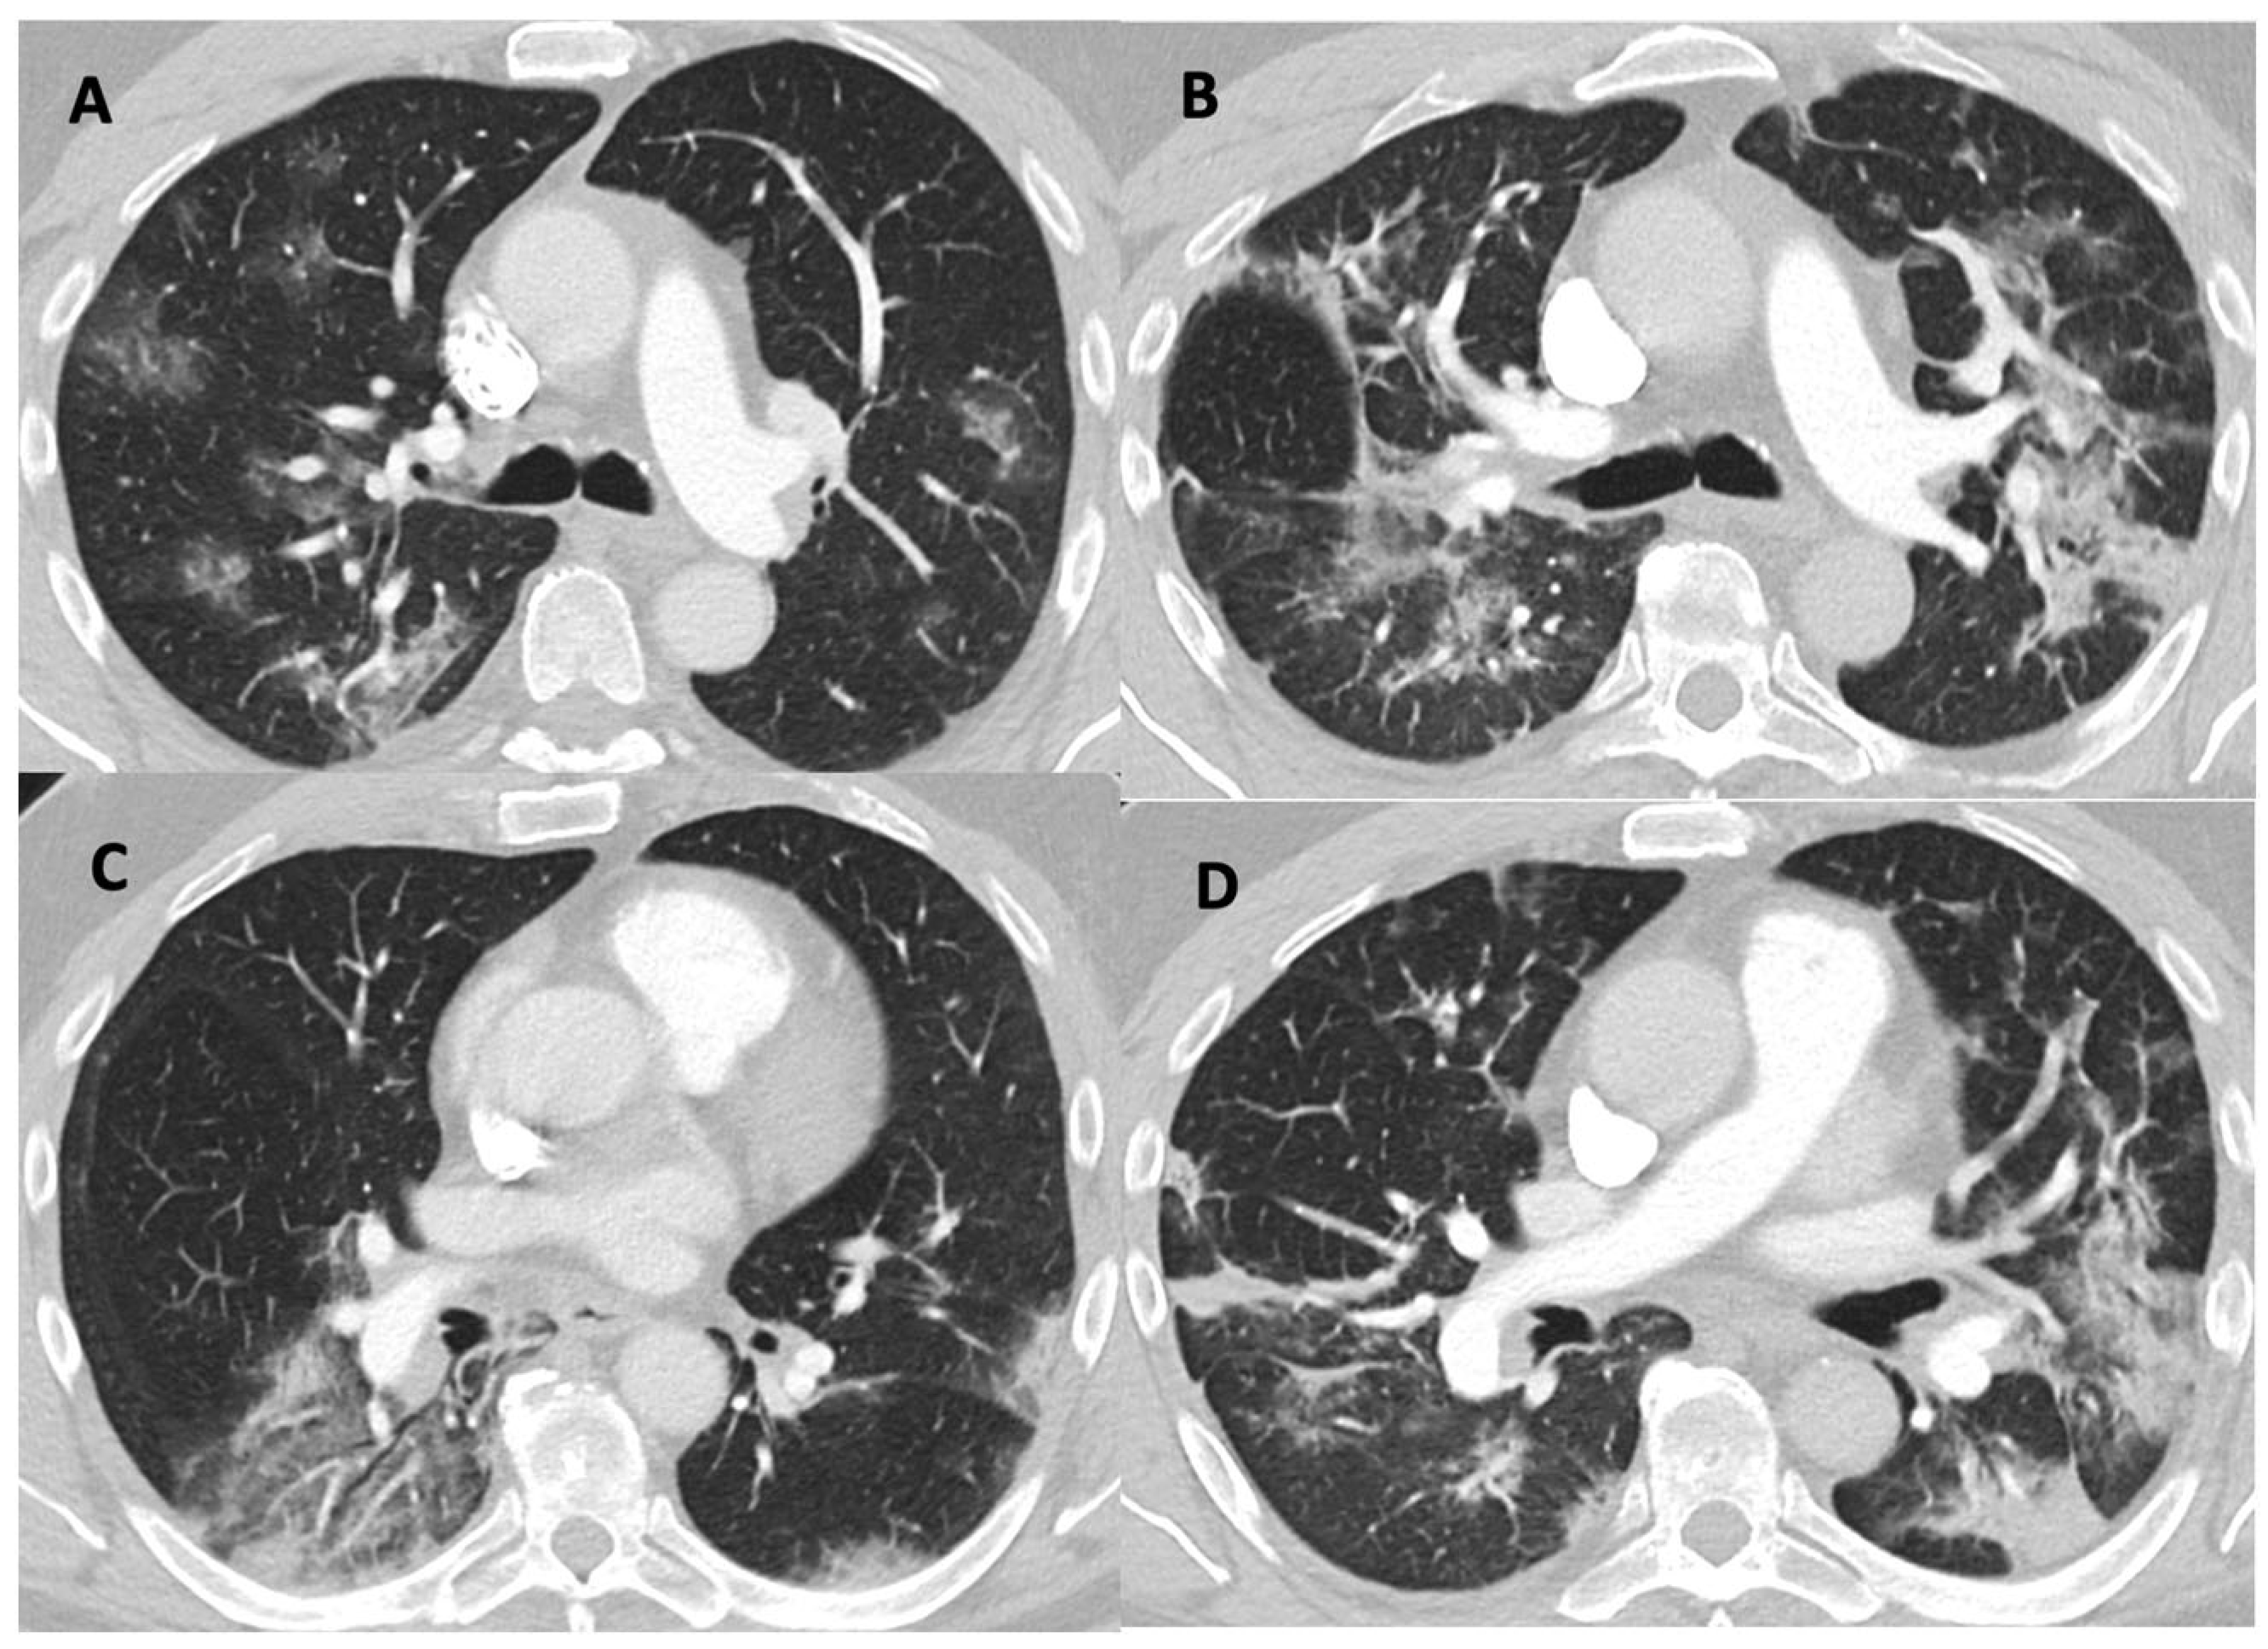

- Barotrauma: One subject in the control group had a pneumothorax. Five subjects had pneumomediastinum, four in the control group and one in the HBOT group.